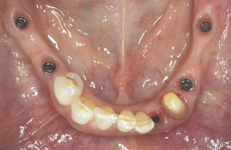

Během let může postupnou ztrátou zubů zůstat v ústech omezený počet zubů, které umožňují držení zubních náhrad.

V důsledku přetížení zbylých zubů např. houpavými pohyb snímacích náhrad dochází k uvolnění těchto zubů a držení můstků a protéz je tak velmi těžké. V těchto případech můžeme pomocí implantátů zvýšit počet pilířů a tím zabránit přetěžování a ztrátě zbylých zubů